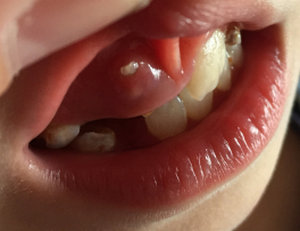

Дочке 7 лет, возраст, когда молочные зубки выпадают. Начал шататься верхний второй зуб слева. Сегодня заметила, что рядом режется зуб, но только совсем не там, где я его ожидала.

Подскажите, можно ли будет как-то исправить ситуацию? Он как-то совсем не там, где нужно растет. Причем, жалоб от нее не поступало, ничего не болело. Честно, я в панике, хочется, чтобы у девочки были красивые, ровные зубки. Что делать?

Не переживайте, обратитесь к стоматологу-ортодонту на очный приём, и удаляйте все молочные зубки под его наблюдением. Данный зуб необходимо как можно раньше удалить, так как нет места для правильного прорезывания постоянного зуба.